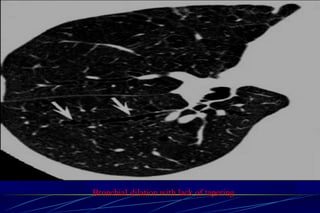

Bronchiectasis

Bronchiectasis is defined as localized bronchial

dilatation. (signet-ring sign)

bronchial wall thickening

lack of normal tapering with visibility of airways in

the peripheral lung

mucus retention in the broncial lumen

associated atelectasis and sometimes air trapping

Signet-Ring Sign

A signet-ring sign represents an axial cut of a dilated bronchus

(ring) with its accompanying small artery (signet).

Tram Tracks

Bronchial dilation with lack of tapering .